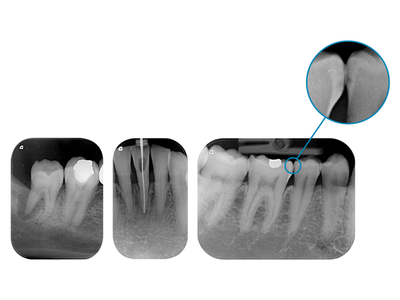

Con un riconoscimento del dettaglio di 40 coppie di linea per millimetro teoriche (LP/mm), 22,7 reali, 1100 dpi e 65.536 livelli di grigio (16 bit), il VistaScan Mini View è lo scanner per film ai fosfori con la risoluzione più alta sul mercato. Grazie a queste performance le informazioni diagnostiche rilevanti sono ancora più visibili.

La tecnologia PCS consente infatti di rappresentare in modo sicuro e affidabile anche i sottili strumenti endodontici sino a ISO 06, così come lesioni cariose di grado D1.